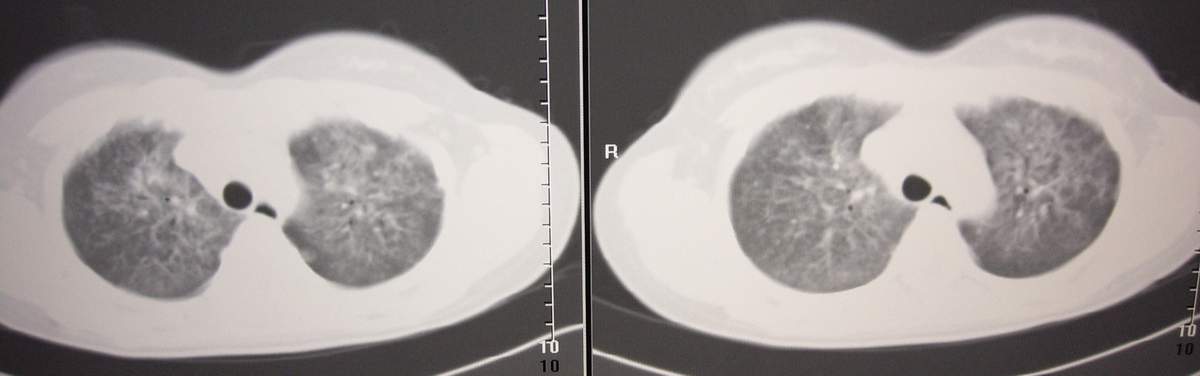

标题: CT7371:[讨论]肺部病变!

女,咳嗽、气喘2月余。

双肺纹理增多,紊乱,呈网格状,期间搀杂斑片及磨玻璃样阴影.考虑;感染性病变_首先考虑:特殊感染:嗜酸性肺病.

双肺弥漫磨玻璃样影,边界不清,似蝶翼征。肺纹理增多。

考虑:肺泡蛋白沉积症。建议临床进一步检查。